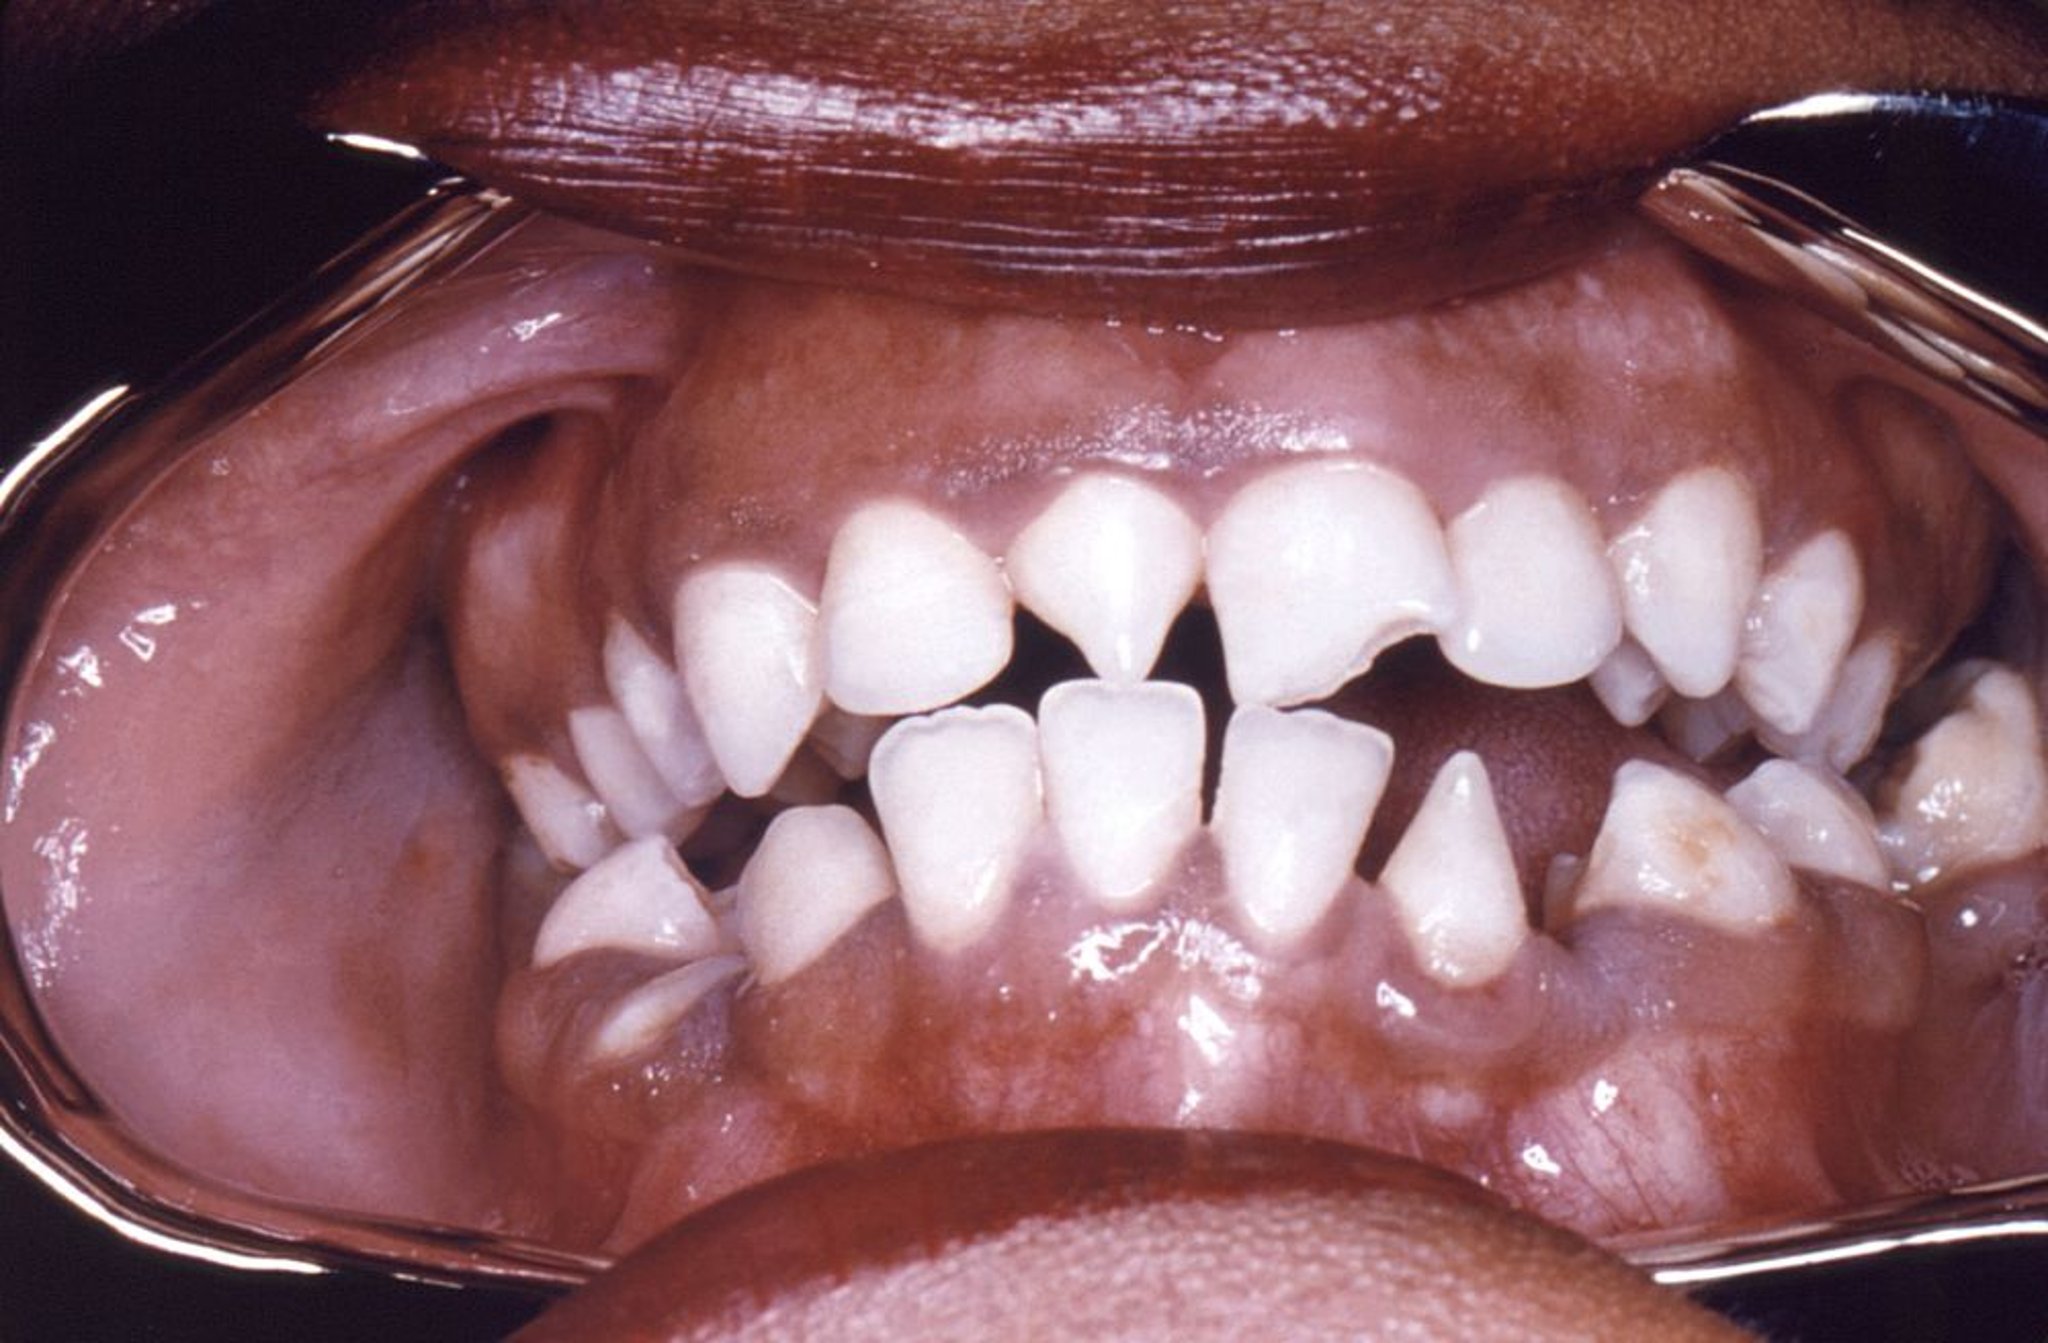

Hutchinson-Schneidezähne

Dieses Foto zeigt eine dreieckige Verformung der rechten oberen und linken unteren Schneidezähne, die durch kongenitale Syphilis verursacht wurde.

Image courtesy of Robert E. Sumpter via the Public Health Image Library of the Centers for Disease Control and Prevention.